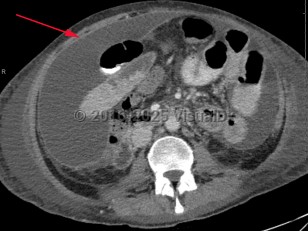

- Primary (spontaneous) bacterial peritonitis – Occurs without an apparent source of contamination and is thought to be secondary to bacterial translocation across the bowel. It is most commonly found in patients with underlying cirrhosis and ascites, but may be found in patients with congestive heart failure, systemic lupus erythematosus, chronic viral hepatitis, or acute viral hepatitis. Presentation can be subtle, and up to 30% of patients may be asymptomatic. Fever is common, but presentation can be marked by altered mental status or abdominal pain in those with cirrhosis. This infection is often paucibacillary, and culture is not uncommonly negative. When an organism is identified, common organisms include Escherichia coli, streptococci, enterococci, and pneumococci.

- Secondary peritonitis – Results from the contamination of the peritoneum from spillage from an intraabdominal viscus, and results in gradually worsening abdominal pain as the parietal peritoneum becomes irritated. Pain, fever, and guarding are common presenting symptoms. Polymicrobial infections are common, including gram positive, gram negative, and anaerobes.

- Peritonitis secondary to ambulatory peritoneal dialysis (PD) – Presents with fever, diffuse abdominal pain, purulence at PD catheter site, guarding, and cloudy peritoneal fluid. Pathogens responsible are commonly skin flora such as Staphylococcus organisms.